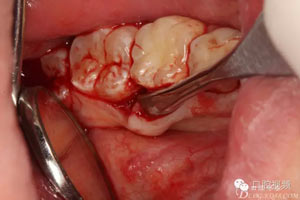

圖6.翻瓣、形成袋形瓣

圖7.通過CBCT準(zhǔn)確定位,暴露35部分牙冠。